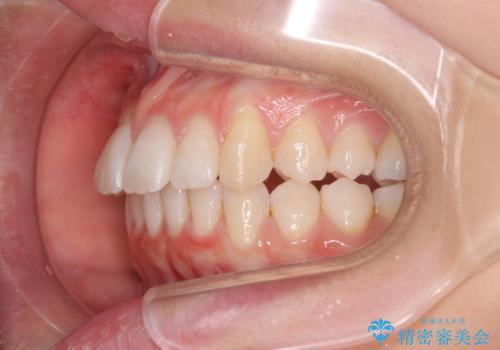

歯を抜かないで出っ歯を治したい

- 前歯が出ていることを主訴に来院。

歯を抜かずにマウスピース矯正をご希望でした。

歯と歯の間をわずかに削り、歯並びを少し横に拡大して並べました。

奥にすき間がなかったため後ろには下げていません。

沢山ひっこめるには4本抜歯でワイヤーの選択肢もありましたが、抜かないでできる範囲をご希望されました。

とがった形の歯列を整えるだけでもだいぶ印象は変わると思います。

今回歯列を広げた結果、上顎犬歯の歯肉は多少退縮しています。